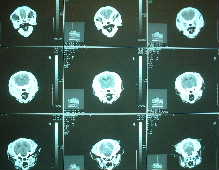

高度専門医療について

動物の医療の現場でも非常に高度な専門治療が近年行われるようになってきました。いままでではあきらめなければならなかった検査や手術が、ごく限られた専門病院で行われています。

当院は一般病院としての設備はほとんど整えていますが、非常に特殊な技術や設備を必要とする治療や検査に関しては、この地方の専門病院を紹介することも飼い主さんの選択肢のひとつと考えています。